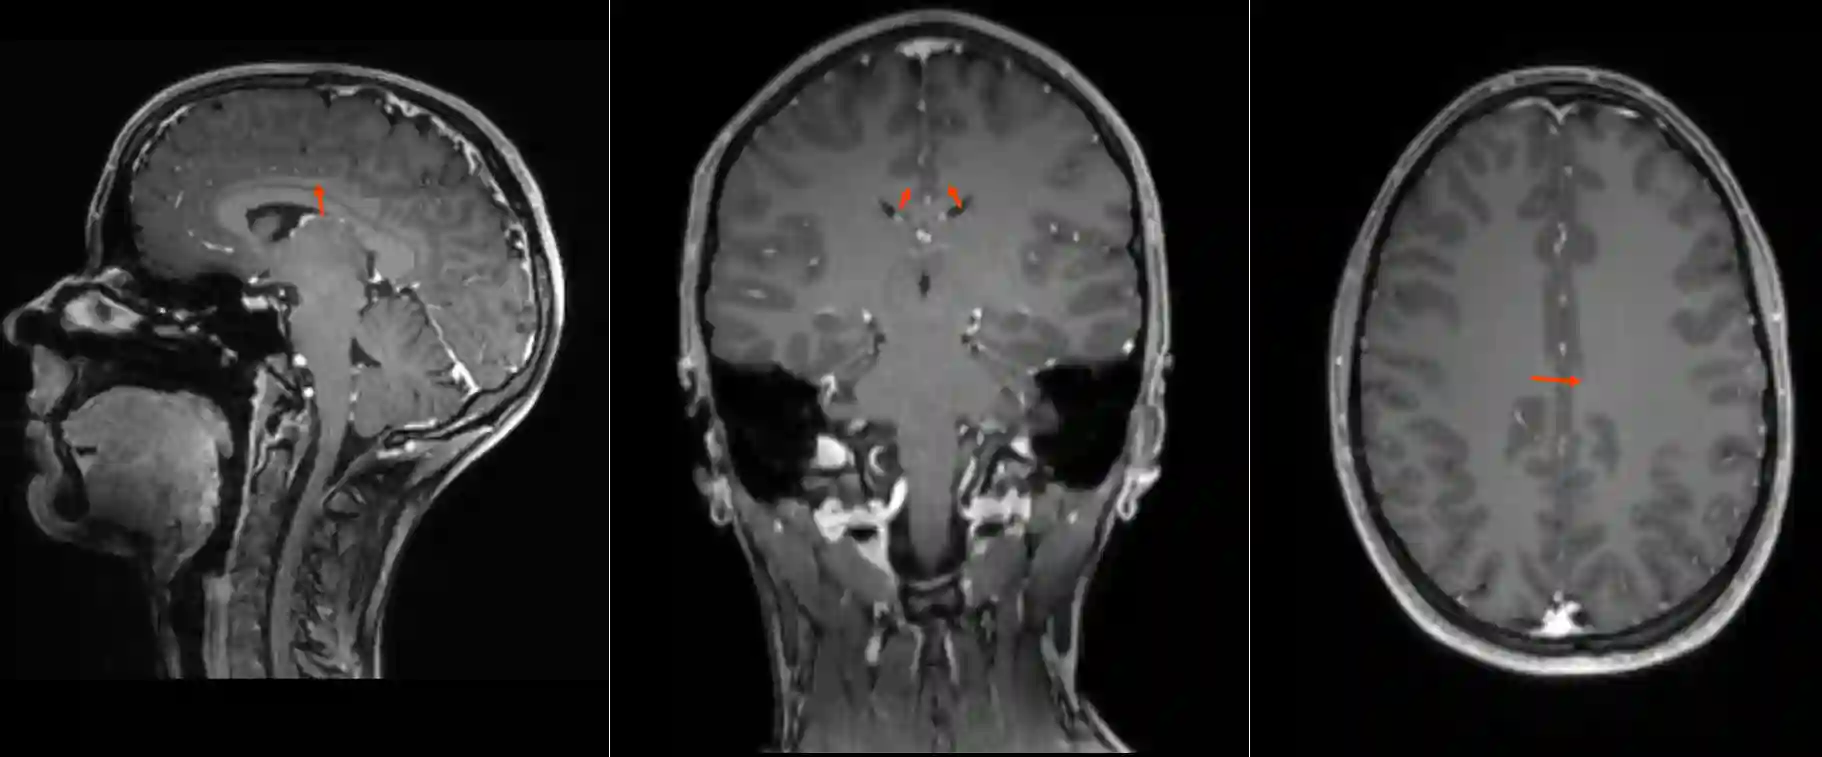

Gyrus cinguli im MRI

Darstellung des Gyrus cinguli (roter Pfeil) in einer T1 Sequenz mit Kontrastmittel im MRI in drei verschiedenen Ebenen.